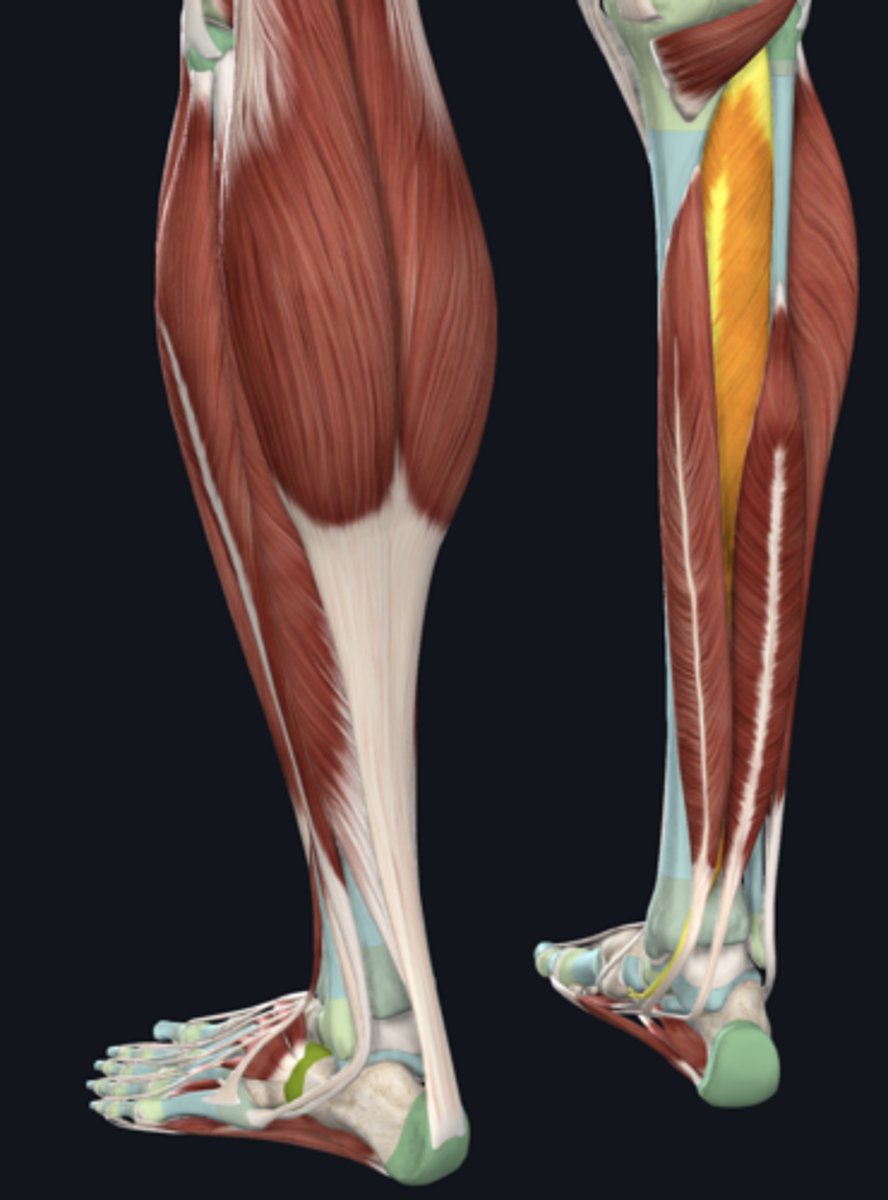

Medial head of gastrocnemius

Lateral head of gastrocnemius

Soleus

Plantaris

Flexor digitorum longus

Flexor hallucis longus

Tibialis posterior